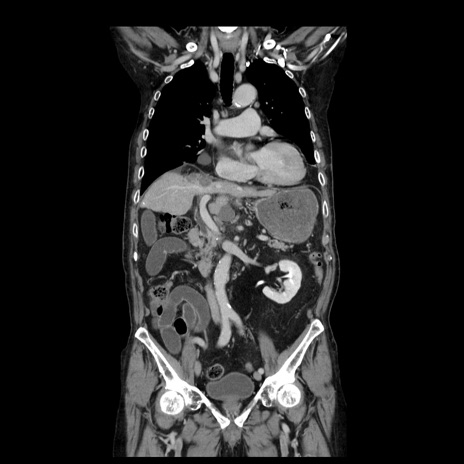

症例21(冠状断像)

【症例】70歳代男性

【主訴】腹痛

【現病歴】肝硬変・肝細胞癌にてかかりつけの方。約9時間前に食後より腹痛出現。症状が徐々に増悪し、嘔吐出現したため来院。

【既往歴】肝硬変、肝細胞癌(RFA、TACE後)

【身体所見】意識清明、表情苦悶様、BT 36℃、BP 129/78mmHg、P 88bpm、SpO2 97%(RA)、右上腹部から心窩部にかけて圧痛あり、反跳痛なし、筋性防御あり。

【データ】WBC 5800、CRP 0.16